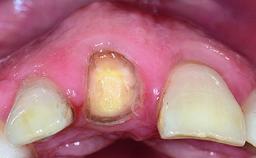

A healthy 37-year-old female patient was referred for a consultation on the replacement of missing tooth 21 with an implant-supported restoration. She stated that several years previously the tooth had been traumatically avulsed following a motor vehicle accident. The tooth was replaced with a three-unit fixed partial denture (FPD) immediately afterwards. Over time, she became disillusioned with the FPD and looked for a different option, including orthodontic therapy. She presented still in her orthodontic appliances, with the pontic sectioned free from the FPD but attached to the archwire. Her orthodontist felt that orthodontic treatment had been successfully completed, but nevertheless referred her before removing the appliances in case adjustments were necessary.

Defining Characteristics One missing tooth to be replaced by an implant-borne crown

Retention Cemented, with prosthesis margin < 3mm submucosal Cemented, with prosthesis margin < 3mm submucosal

Esthetic Risk High

Soft Tissue Contour and Volume Slightly compromised